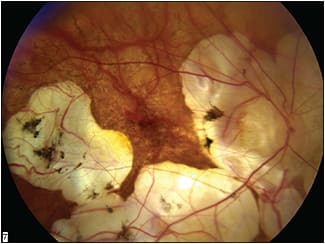

Following successful axial myopia stabilization, myopic degeneration is expected to still progress, at a rate that is appropriate for the degree of myopia present and the particular features of the eye in question. The earlier the diagnosis can be made and treatment given, the better the opportunity will be to influence the future course of vision in a positive manner (Figure 7).

Figure 7. Buckling at a very late stage in the progression of degenerative myopia in an attempt to slow vision loss in an eye with a poor prognosis.